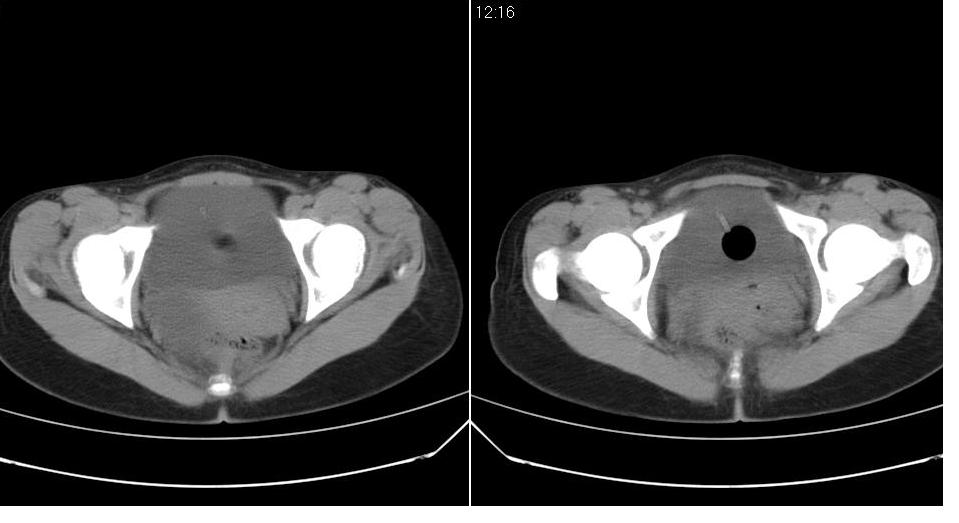

标题: CT22811:女 36岁,B超提示右侧附件囊性占位。 [打印本页]

标题: CT22811:女 36岁,B超提示右侧附件囊性占位。

先考虑---卵巢囊肿。

子宫内膜增厚---可能是卵巢激素紊乱造成的。

手术结果证实为右侧输卵管囊肿。

输卵管囊肿罕见,从影像上无法同卵巢囊肿区分。

输卵管囊肿一般是指输卵管受病原体感染以后,由于白细胞的浸润形成内膜肿胀、间质水肿、渗出,输卵管粘膜上皮脱落,如果输卵管急性期炎症没得到及时有效的治疗就形成了输卵管积脓。输卵管积脓在炎症消退后,脓液逐渐被吸收,腔内积液由脓性变为浆液性,则成为输卵管囊肿。

还是报右侧附件区良性囊性占位性改变       至于输尿管或卵巢囊肿不太好鉴别